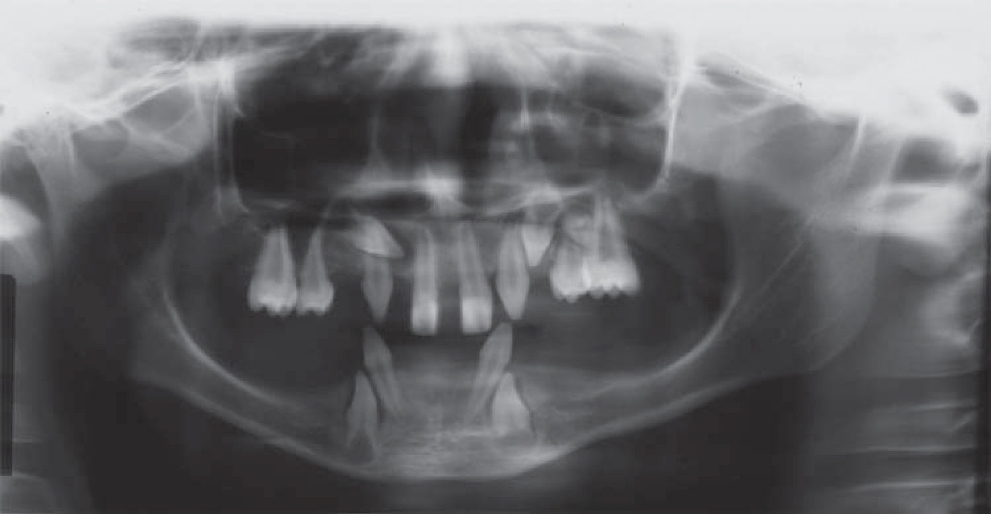

Los exámenes auxiliares más utilizados para este tipo de anomalía son las radiografías panorámicas con el fin de determinar presencia de gérmenes dentarios y anomalías dentarias, observándose dentro de estos últimos oligodoncia, dientes con alteración de forma, principalmente dientes en forma cónica y marcada reabsorción ósea horizontal generalizada. En la mayoría de los casos, los dientes presentes son incisivos superiores, caninos inferiores y superiores, con menor presencia de premolares.2,3,11

El paciente fue sometido a documentación radiográfica inicial, obteniéndose radiografías panorámicas, telerradiografía, oclusal total de maxila (Figuras 2 a 4) (3). En la evaluación radiográfica se observaron agenesias dentarias múltiples, además de las piezas dentarias observadas en el examen intraoral, se presentaban los caninos superiores (derecho e izquierdo) en erupción; germen dentario a nivel del primer premolar superior izquierdo y caninos inferiores en erupción, posiblemente ambos con alteración de forma de la corona dentaria; reabsorción ósea generalizada en ambas arcadas.

Figura 2. Radiografía lateral mostrando ausencia del proceso alveolar en regiones edéntulas de maxila y mandíbula.

Dentro de los exámenes auxiliares más utilizados para este tipo de alteración están las radiografías extraorales: panorámica y telerradiografía, así también suelen ser usadas radiografías intraorales como la oclusal total y periapical, con el fin de determinar presencia de gérmenes dentarios, reabsorciones óseas, perfil óseo y disposición de piezas dentarias en la maxila como en la mandíbula, con estas referencias la literatura reporta que los dientes permanentes más comúnmente ausentes en individuos portadores de DEH son los incisivos laterales, premolares y segundos y terceros molares. Los dientes más estables son los incisivos centrales superiores, los caninos y primeros molares superiores e inferiores.3,11,13Los incisivos laterales superiores son los dientes inestables comúnmente más ausentes, seguidos de los incisivos centrales inferiores y los dientes más afectados por alteraciones morfológicas son también los incisivos centrales superiores y caninos.14,15El caso que se presenta muestra presencia de los cuatro incisivos superiores con alteración de forma, dientes conoides, caninos superiores en erupción con aparente forma conoide, primeros premolares y primeros molares superiores con taurodoncia, germen dentario del segundo premolar superior izquierdo, ya en la mandíbula se observó la presencia de los incisivos laterales con forma conoide y caninos inferiores en erupción con aparente alteración de forma coronaria de tipo conoide. Se pudo observar también la marcada reabsorción ósea horizontal en ambas maxilas.